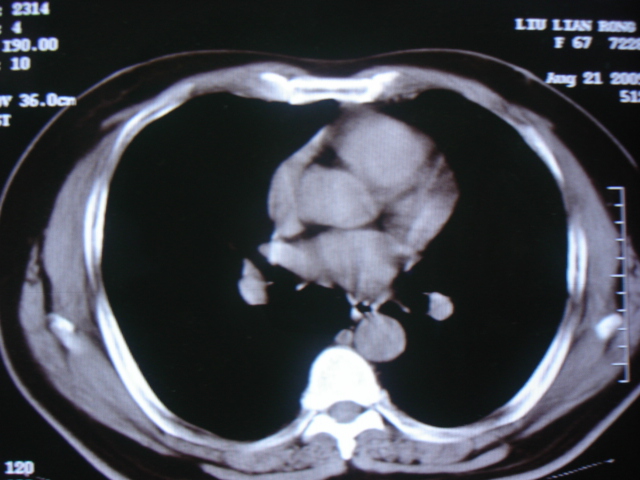

第一次ct2009.6.4

第二次ct2009.6.7 住院后ect未见异常,查痰(阴性)大量抗菌素抗炎一个月后病灶明显变小,7月5号出院后回家后口服抗菌素45天

第三次ct2009.8.21

病灶与胸膜成直边征,考虑炎症假瘤可能性大。

炎症,最厚一次已吸收

考虑左肺上叶炎症感染(炎性假瘤可能)。

考虑 左肺上叶炎症感染 [炎性假瘤可能性大]。

考虑左肺上叶炎症感染,以炎性假瘤可能性大。